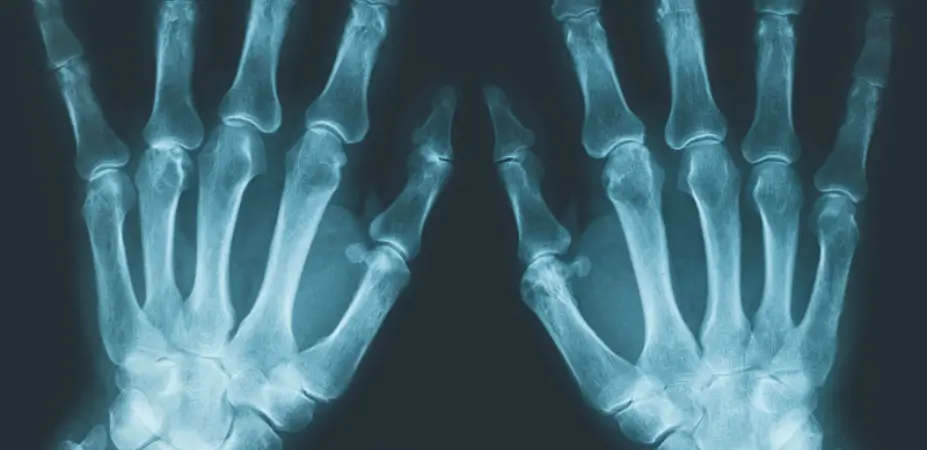

X-ray of hands

Medical X-Rays

We can scan any size of x-rays from 14″ x 17″ down to 44mm. X-Ray’s can be captured using a photographic procedure or using specialist X-Ray scanning equipment.